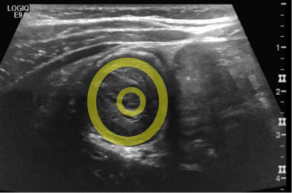

Answer:  Intussusception

• Imaging may includes plain xrays demonstrating signs of bowel obstruction, but ultrasound should be considered as well. Ultrasound demonstrates the “target sign” demonstrated below